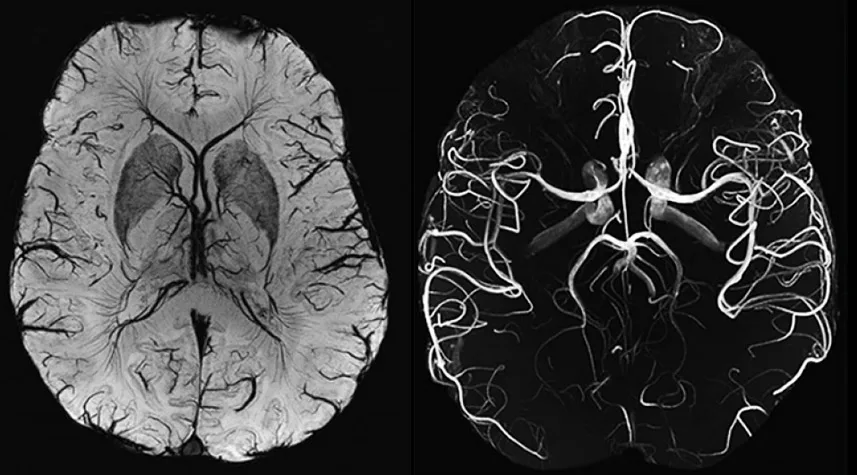

Магнитно-резонансная томография (МРТ) артерий головного мозга https://www.neuromed.ua/ru/services/mrt-arteryy-holovnoho-mozgha/ — это неинвазивное диагностическое исследование, позволяющее получить высокоточные изображения сосудов, питающих мозг. В отличие от классической МРТ, ангиография акцентирует внимание именно на состоянии артериальной сети. Метод используется для выявления патологий кровоснабжения, таких как аневризмы, стенозы, тромбозы и мальформации.

МРТ основана на явлении ядерного магнитного резонанса. Под действием магнитного поля и радиочастотных импульсов атомы водорода в тканях организма начинают излучать сигналы, которые регистрируются и преобразуются в детализированные изображения. МР-ангиография (МРА) использует специальные протоколы, выделяющие ток крови внутри сосудов, делая артерии головного мозга отчетливо видимыми на снимках.